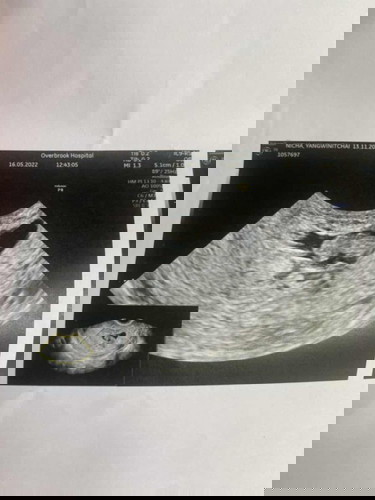

ซาวแล้ว หมอบอกว่าเสียชีวิตแล้ว

ขออนุญาตค่ะ ท้องได้ 8-9 สัปดาห์ พอดีวันจันทร์ที่ผ่านมากะว่าจะไปฝากท้อง แต่หมอซาวก่อน เจอตัวเด็ก แต่หัวใจไม่เต้น หมอเลยสรุปว่าน่าจะเสียชีวิต 3 สัปดาห์แล้ว หมอให้เลือกว่าจะขูดออก หรือ ให้หลุดเอง ปรึกษากับครอบครัวแล้ว เขาให้ขูดออกค่ะ 🥺 มีใครเคยเจอแบบนี้มั้ยคะ. ขูดมดลูกเจ็บมั้ยคะ หมอใช้ยาสลบมั้ยคะ #ขอบคุณสำหรับคำตอบค่ะ #คุณแม่ๆช่วยแนะนำหน่อยค่ะ

วันนี้หมอตรวจซ้ำให้แล้วค่ะ น้องเสียชีวิต แล้วจริงๆค่ะ